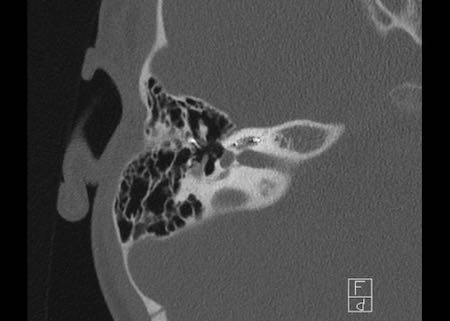

Bên trái là hình ảnh của một bé gái 2 tuổi.

Các hình ảnh từ kết quả chụp CT được thực hiện trước khi cấy ốc tai điện tử.

Quan sát thấy dị dạng nhẹ ở đỉnh ốc tai – không có sự phân tách giữa vòng thứ hai và vòng thứ ba, và trụ ốc tai xương vắng mặt.

Cống tiền đình bình thường.